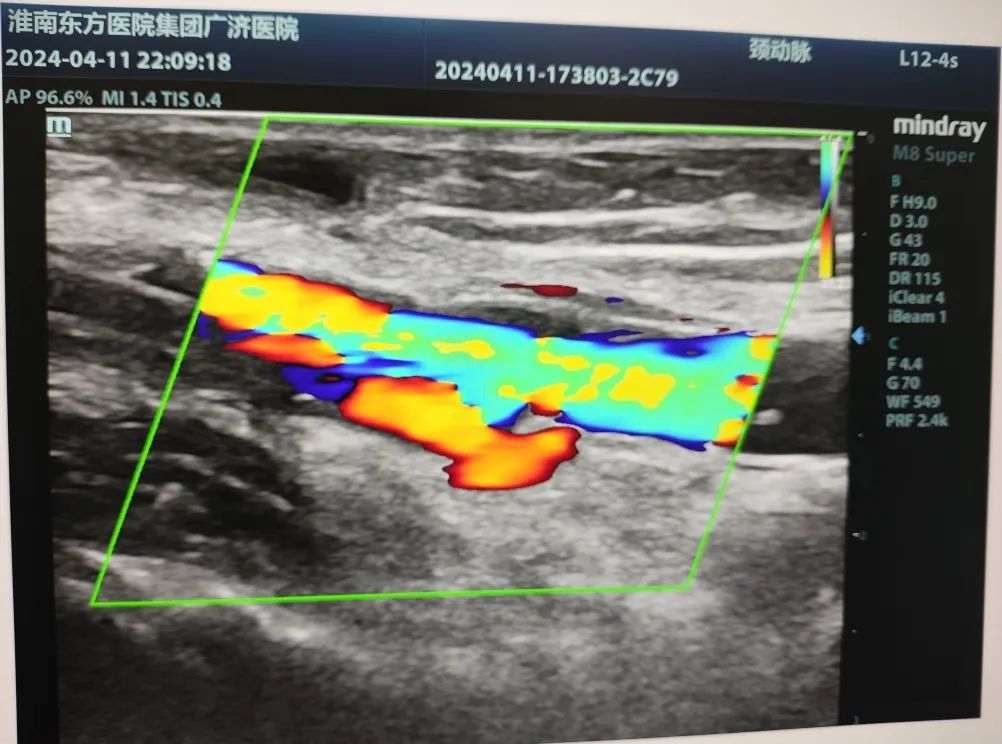

▲再通后

作为一名专业的透析通路医生,魏然主任首先为其详细评估两侧动静脉内瘘,彩超探查,右前臂动静脉内瘘大量血栓形成,左前臂动静脉内瘘血栓形成。急查双上肢动、静脉+多普勒血流图:右侧动静脉内瘘吻合口至头静脉弓锁骨下静脉汇入点处全段血栓形成。左侧桡动脉闭塞,左侧前臂头静脉血栓形成。

“左侧老瘘前臂桡动脉、头静脉血栓,右侧新瘘血栓形成距离更长,贵要静脉、上臂头静脉、锁骨下静脉都不乐观。”考虑到患者远期通畅率及经济压力等问题,魏然主任为患者制定了两套手术方案,首选打通左前臂血栓闭塞2年的“老瘘”。完善术前准备后,魏主任第一时间安排手术,在无影灯下,他手持超声探头,熟练操作,一点一点清除血栓开通闭塞,终于闭塞2年之久的内瘘再通了。“虽然难度大,但是手术顺利,放心吧。”